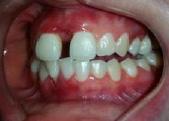

Lâexamen exobuccal Ă©tait sans particularitĂ©s. Lâexamen endobuccal a objectivĂ© une inflammation marginale modĂ©rĂ©e Ă sĂ©vĂšre gĂ©nĂ©ralisĂ©e avec un indice dâOleary Ă 68%, un indice gingival (BoP = Bleeding on Probing) Ă 76%, et un trama occlusal sur 42 (Figure 1). Le bilan parodontal montre des sites avec une profondeur de sondage (PS) de 12mm, et plus de 50% des dents prĂ©sentant une perte dâattache â„ 5mm. Le bilan radiographique a montrĂ© des pertes osseuses terminales, avec un rapport perte osseuse/Ăąge Ă 4,5 (Figure 1)

Le diagnostic de parodontite stade IV grade C généralisé a été proposé (1), avec un pronostic irrationnel au traitement pour les dents 25, 36, 42 et défavorable pour 11, 21, 35, 46 (2).

La thĂ©rapeutique Ă©tiologique a consistĂ© en une Ă©ducation Ă lâhygiĂšne bucco-dentaire, une Ă©limination des facteurs de rĂ©tention de plaque, lâextraction 42+rĂ©section radiculaire et rĂ©alisation dâune contention en fibre de verre avec la couronne ; dâune instrumentation non chirurgicale supra et sous gingivale

par quadrant (3) combinĂ©e Ă une antibiothĂ©rapie (3,4). Une chirurgie avec lambeau dâaccĂšs selon la technique du lambeau avec incision intrasulculaire (open flap) a Ă©tĂ© rĂ©alisĂ©e sur la 46. Une thĂ©rapie parodontale de soutien associĂ©e Ă une phase correctrice a Ă©tĂ© mise en place aprĂšs la thĂ©rapie parodontale active (5). La rĂ©habilitation orale a consistĂ© dans un premier temps Ă rĂ©aliser une correction orthodontique (Figure 2) ; et dans un second temps la conception dâune Ă©pithĂšse gingivale (Figure 3)

AprĂšs 6 mois, pas de profondeurs de poches â„ 6mm, avec un indice de plaque Ă 9% et un indice gingival < 10%. La thĂ©rapeutique non chirurgicale a permis un gain dâattache

stable qui sâest traduit par une diminution des profondeurs de sondage en regard de la 11, 21, et 36 dont le pronostic Ă©tait dĂ©favorable, mais aussi lâapparition dâimportantes rĂ©cessions postthĂ©rapeutique (Figure 4). La chirurgie avec lambeau dâaccĂšs a permis Ă©galement dâamĂ©liorer le niveau osseux de la 46. Le pronostic gĂ©nĂ©ral Ă long terme de la patiente a Ă©tĂ© amĂ©liorĂ©.

Figure 4 : (a) Vue clinique Ă 6 mois ; (b) bilan radiographique Ă 3mois (b) ; (c) Retro alvĂ©olaire sur la 46 avant et aprĂšs lambeau dâassainissement